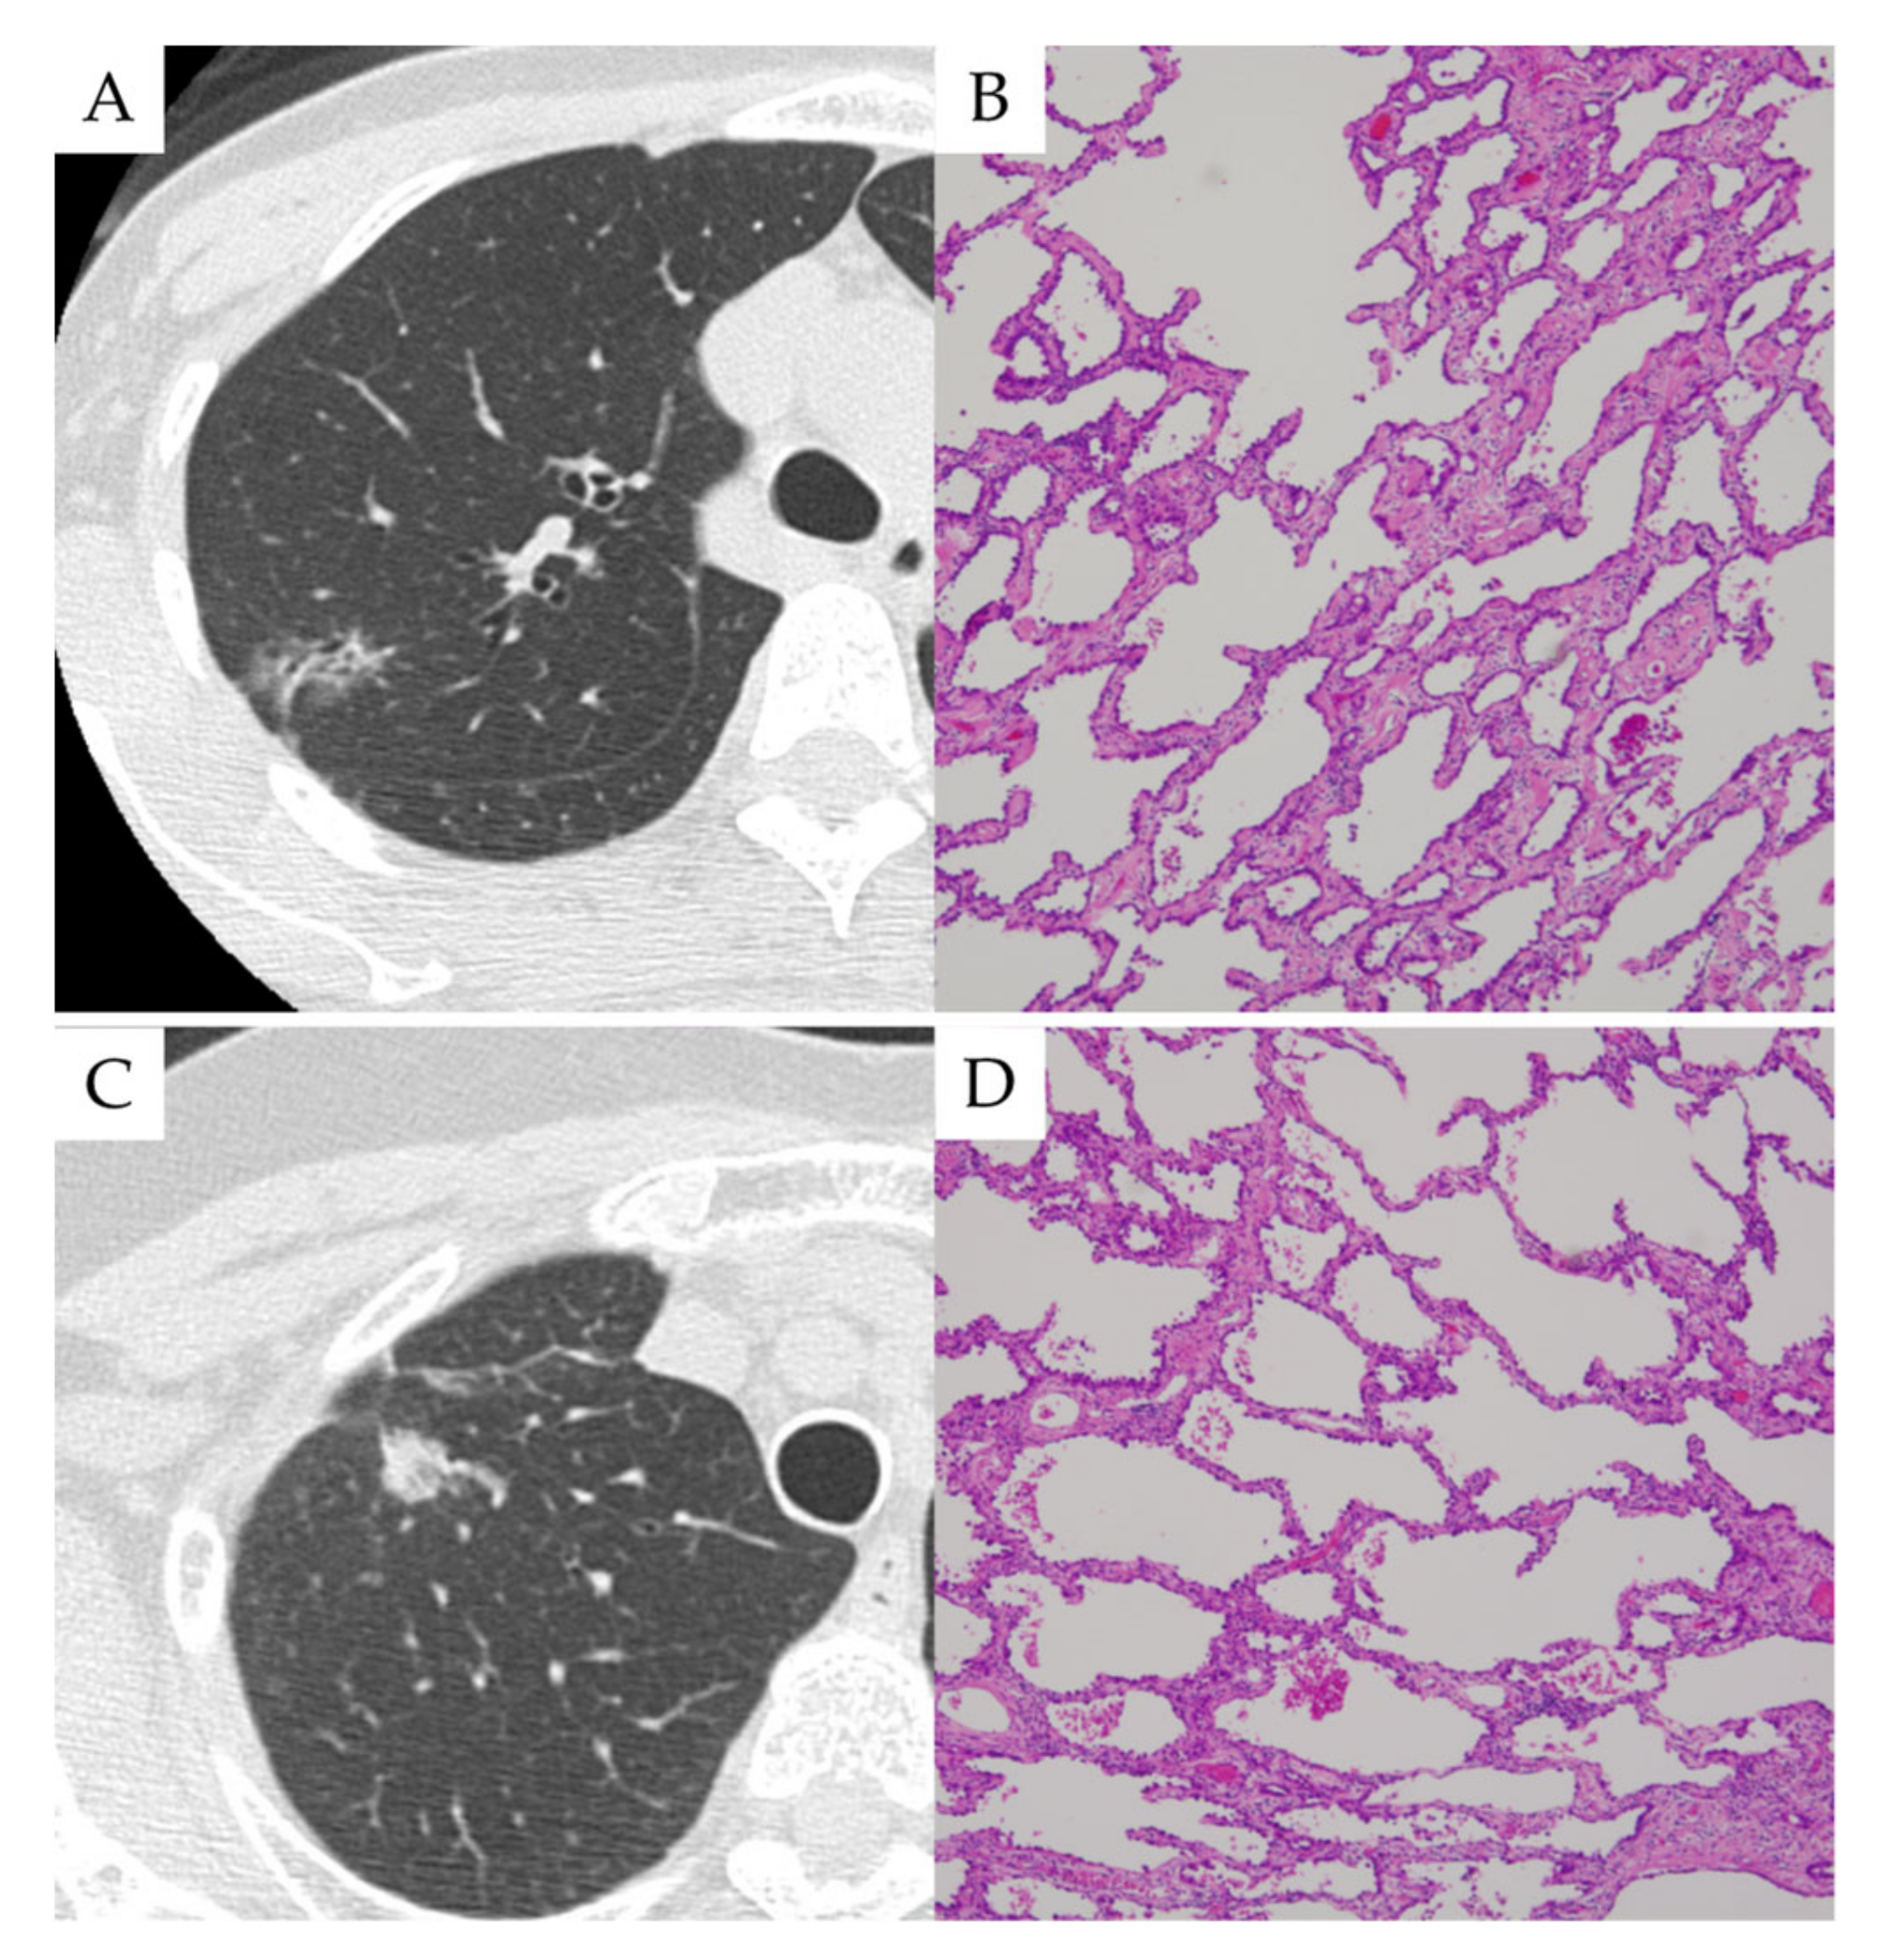

3.2. Case Presentations